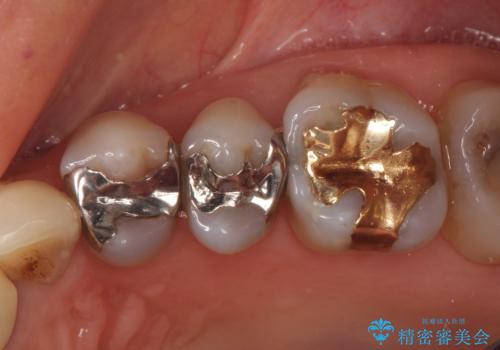

銀が目立つので白くしたい

担当医 青山卓弘